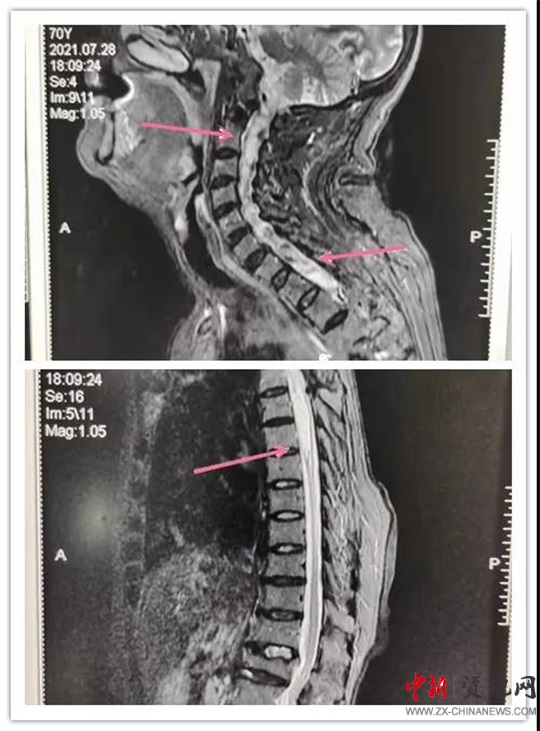

患者,女,70歲,六年前患脊髓空洞癥在某醫(yī)院行“脊髓空洞蛛網(wǎng)膜下腔分流手術(shù)”后病情好轉(zhuǎn)。近段時(shí)間,因“后肩部疼痛,無痛溫覺喪失,雙下肢疼痛、無力逐漸加重”癥狀加重,來汝南縣人民醫(yī)院就診,行MR檢查診斷為“頸胸脊髓空洞”。神經(jīng)外科副主任沈明輝認(rèn)真研究了患者的病情和 MR片子,認(rèn)為手術(shù)可行,隨即收住患者到科室;颊呷朐汉,完善了術(shù)前檢查,由于患者年事已高,患有高血壓、心臟病等疾病,使病情更加復(fù)雜,手術(shù)難度風(fēng)險(xiǎn)進(jìn)一步加大。手術(shù)團(tuán)隊(duì)組織了全科會(huì)診,對(duì)患者手術(shù)情怳進(jìn)行了分析。如果不做手術(shù),病情進(jìn)一步發(fā)展,患者雙下肢會(huì)截癱,再做手術(shù)也很難恢復(fù)。在得到患者家屬的理解和支持后,根據(jù)患者的病情,手術(shù)團(tuán)隊(duì)反復(fù)討論術(shù)中可能出現(xiàn)的問題:完善圍手術(shù)期應(yīng)急預(yù)案,制定精準(zhǔn)的治療及手術(shù)方案,擇期為患者成功實(shí)施了“頸胸脊髓空洞胸腔引流”手術(shù)。術(shù)后患者雙下肢肌力明顯好轉(zhuǎn),正在康復(fù)中。

手術(shù)前

手術(shù)后